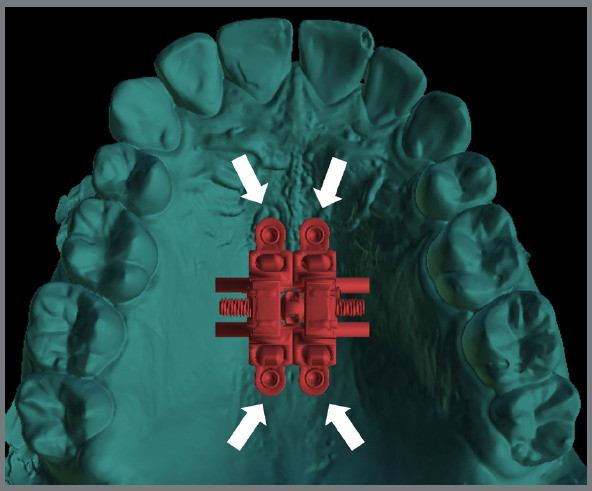

Objective: This cross-sectional study evaluated the bone thickness on mini-implants insertion site, the factors that influence the digital planning of MARPE appliance (miniscrew-assisted rapid palatal expansion), and its different designs.

Methods: A total of 135 plannings were assessed regarding the size of the expander screw used, the positioning and the type of the mini-implant rings, and their location in relation to the teeth. Bone thickness measurements were assessed in the region of the mini-implants' trajectory. Differences between the sexes was verified using the ANOVA test (5% significance).

Results: 73 cases were planned with 4 mini-implants and 62 cases, with 6 mini-implants. In 90% of cases, teeth #16 and #26 were used as supports, and the most used expander screw was 13mm (64.1% of cases). The anterior mini-implants of conventional MARPE showed more pronounced insertion in bone in males (5.9 ± 2mm; p= 0.025). The extra mini-implants (anterior region) were inserted with greater bone thickness in males (11.1 ± 2.3mm) compared to females (9.9 ± 1.8mm; p=0.041). A greater bone thickness was observed in males (10.1 ± 2.1 mm) when using mini-implants in the paramedian region.

Conclusion: Additional rings allow more pronounced bone insertion. Male patients had greater bone thickness, which may be related to greater difficulty in opening the sutures. The alveolar process region seems to be a satisfactory site for mini-implants to those patients with reduced bone thickness in the paramedian posterior region. MARPE appliance must be customized for each patient, due to bone thickness and anatomical variations.